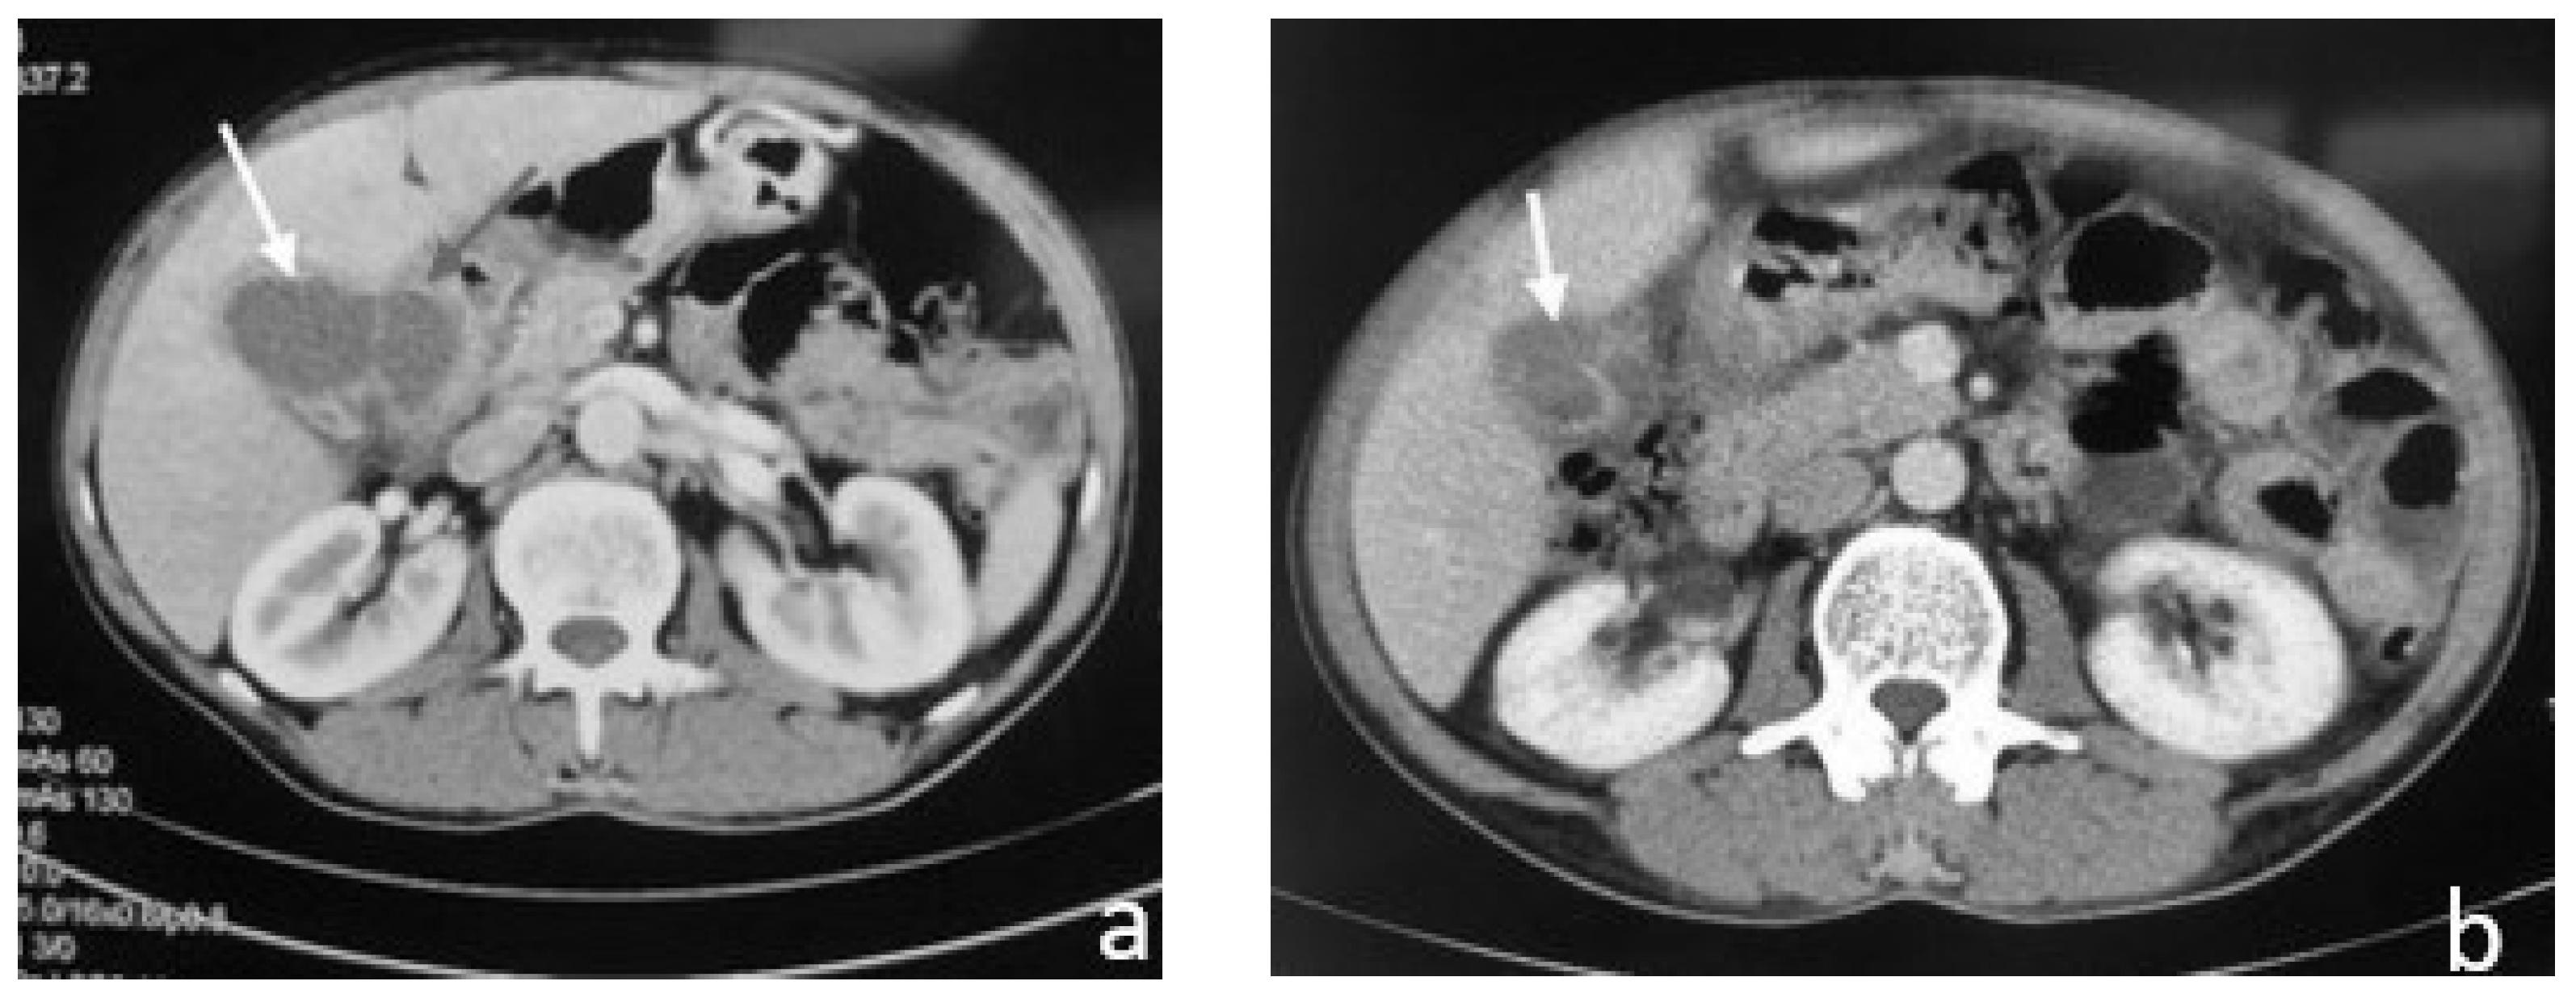

2.1. Case 1

2.2. Case 2

2.3. Case 3